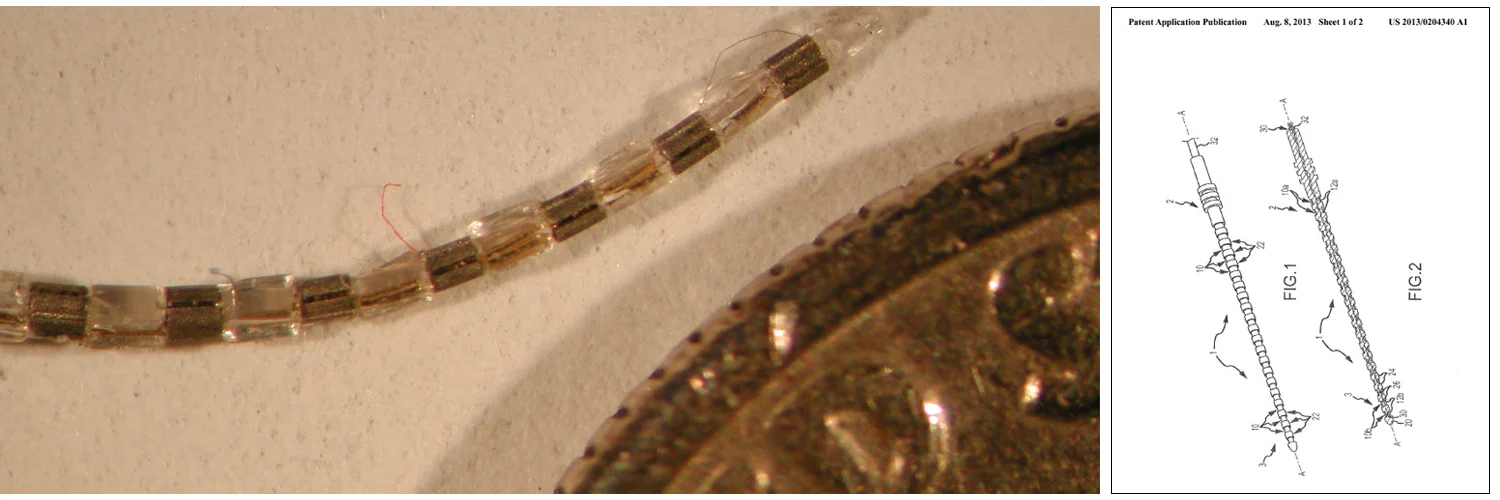

Cochlear Implant

Designed and developed cochlear implant modules which significantly simplify surgical implantation and lower the electrode array manufacturing cost. Developed for a new type of cochlear implant which incorporates the microphone and speech processor within the implant, eliminating the external over-the-ear portion of the device. Patent application #20130204340, “Neurostimulation electrode array and method of manufacture”.